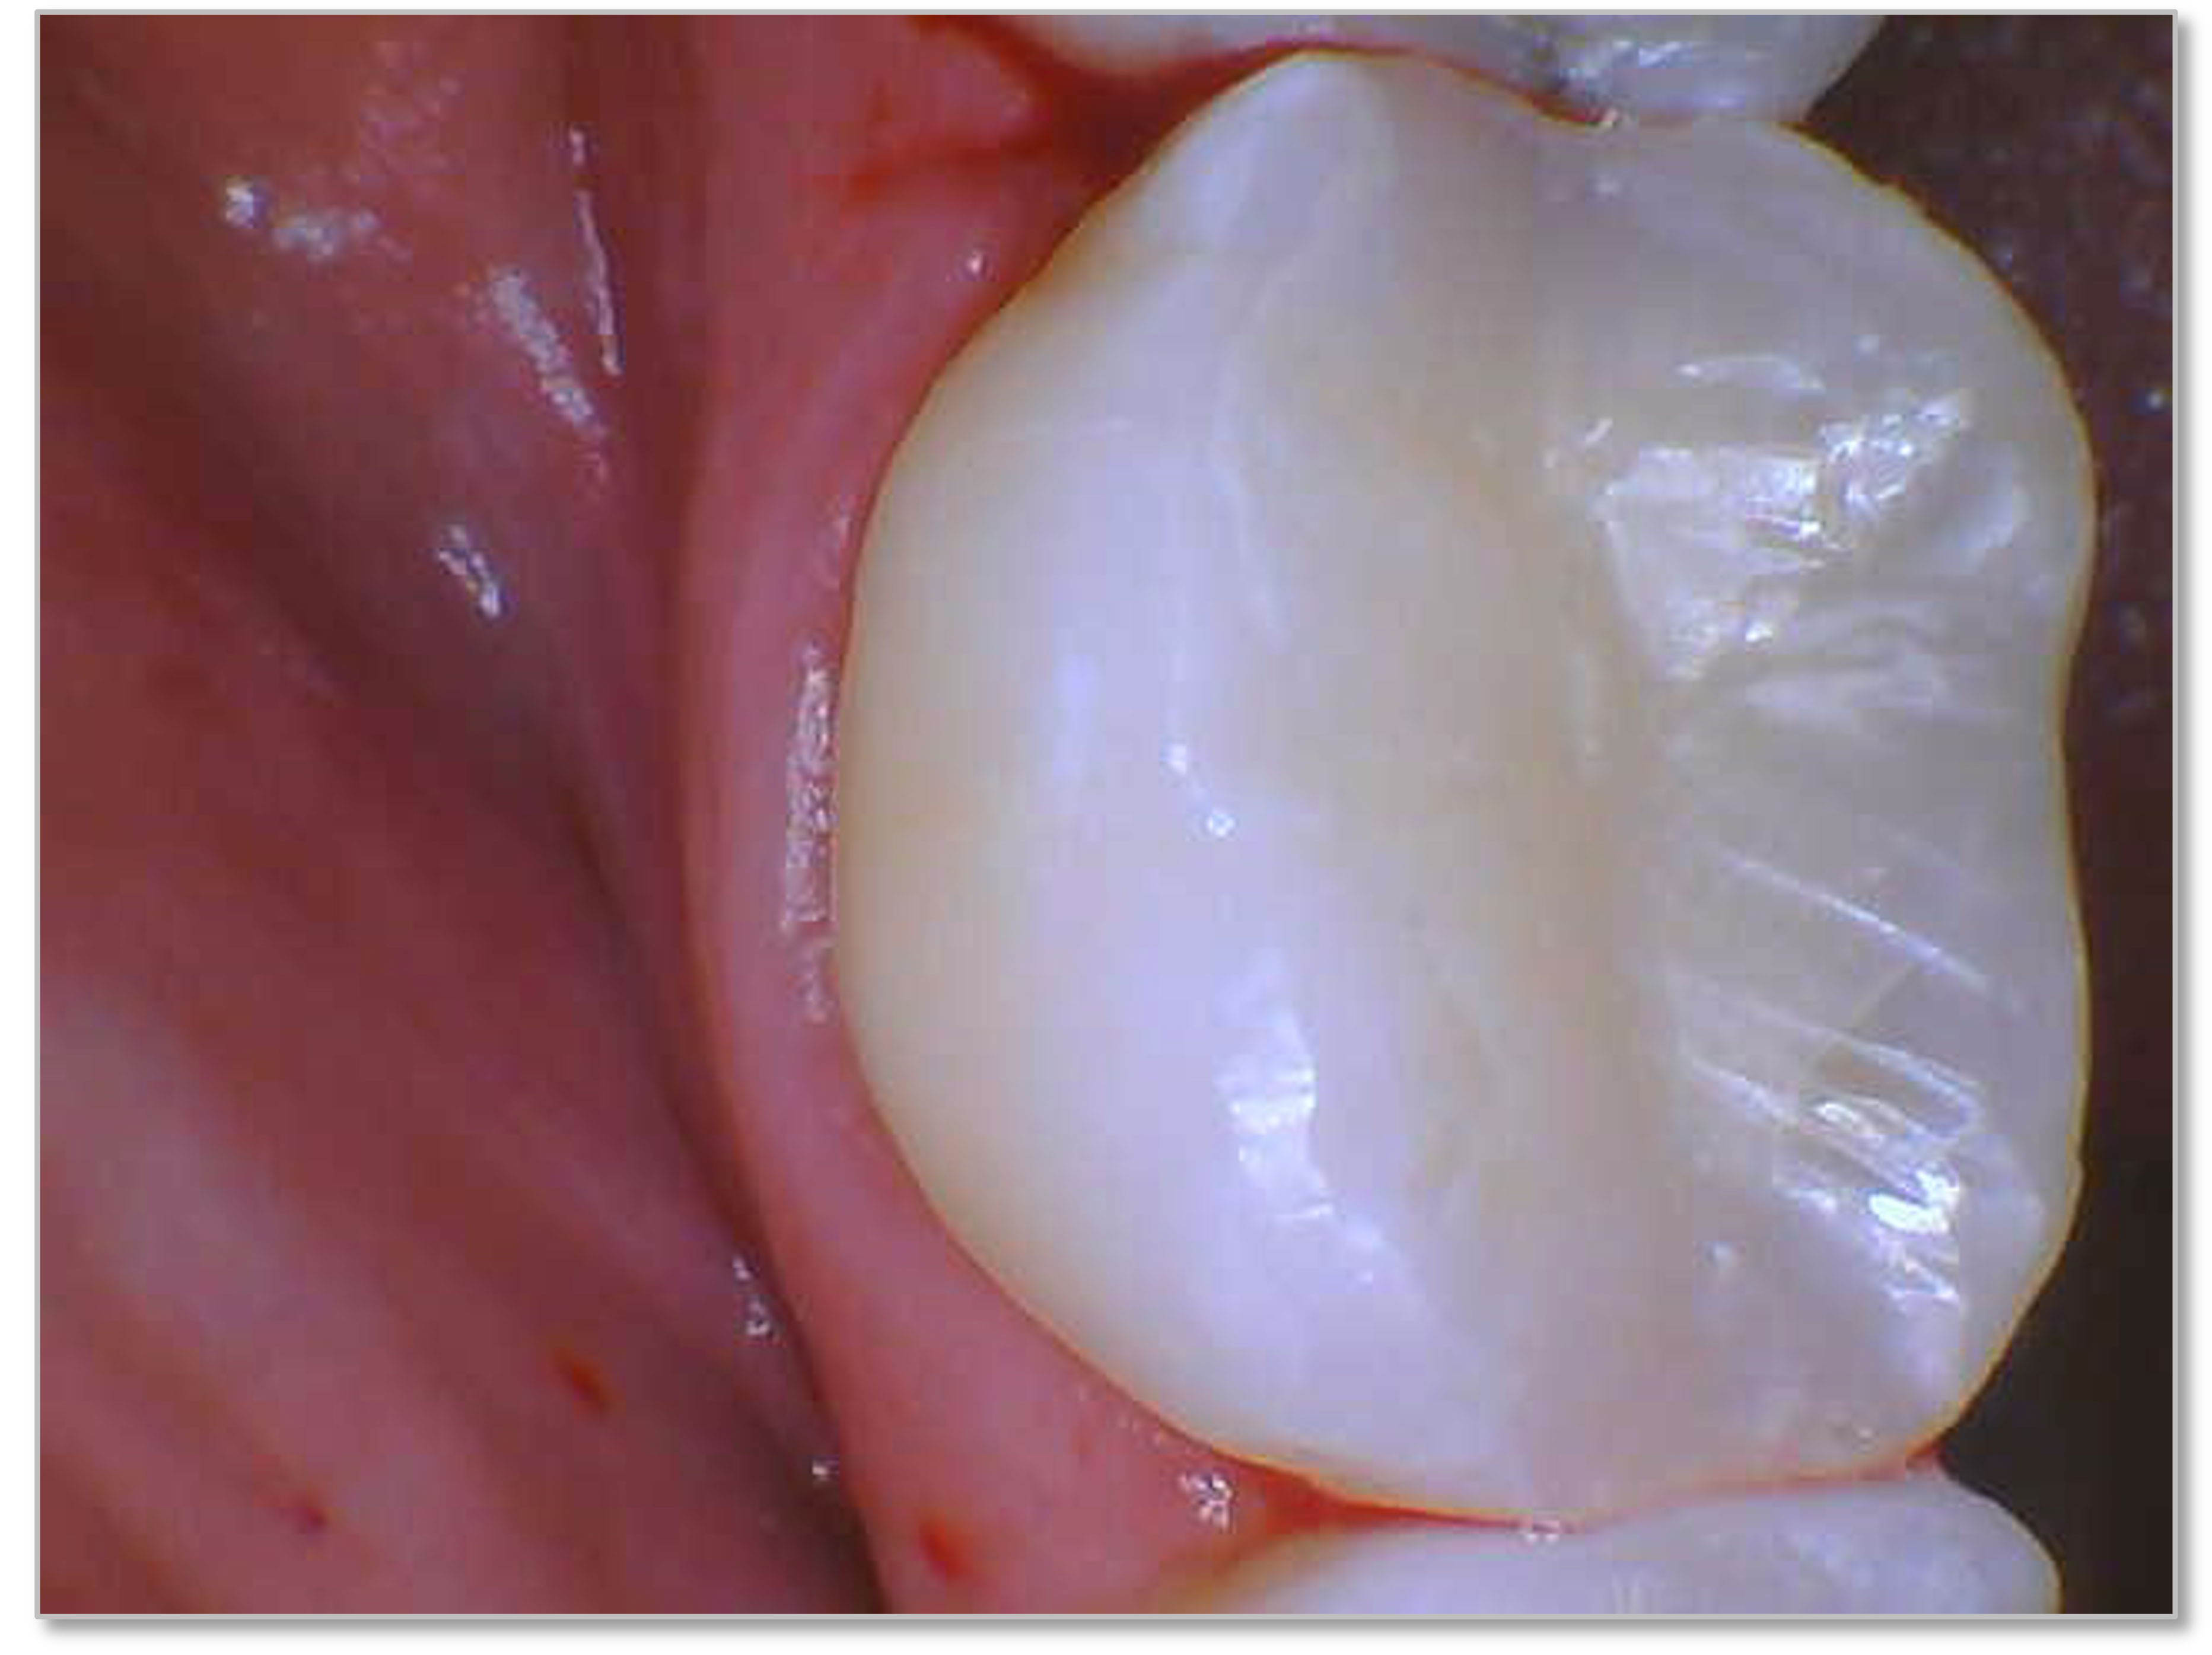

In another case, bulk fill work was done on a Class 5 restoration with a single shade system (Figure 5a and Figure 5b). While one expects more ideal characterization in a system that has more than one shade, this one-shade composite worked very well to blend and match the natural characteristics of the tooth.

Fig 5a. Kerr SimpliShade Bulk Fill one-shade composite is used to blend and match the natural characteristics of the tooth.

Fig 5a.

Fig 5b. Kerr SimpliShade Bulk Fill one-shade composite is used to blend and match the natural characteristics of the tooth.

Fig 5b.